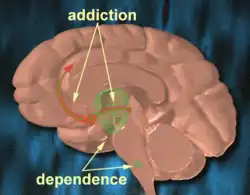

A dopamina (DA, uma contração de 3,4-di-hidroxifenetilamina) é um neurotransmissor monoaminérgico, da família das catecolaminas e das feniletilaminas que desempenha vários papéis importantes no cérebro e no organismo. Os receptores de dopamina são subdivididos em [[Receptor D1 de dopamina|D1], D22, D3, D4 e D5, de acordo com localização no cérebro e função. O cérebro contém várias vias dopaminérgicas, como a via mesolímbica, que desempenha um papel importante no sistema de comportamento motivado a recompensa.[3] [4] A maioria das recompensas aumentam o nível de dopamina no cérebro, e muitas drogas viciantes aumentam a atividade neuronal da dopamina. A dopamina é produzida especialmente pela substância negra e na área tegmental ventral (ATV). A dopamina também está envolvida no controle de movimentos, aprendizado, humor, emoções, cognição e memória.[5]

- Via mesolímbica: sabe-se que a dopamina está relacionada ao pensamento. Esquizofrenia envolve aumento da atividade dopaminérgica nessa via.